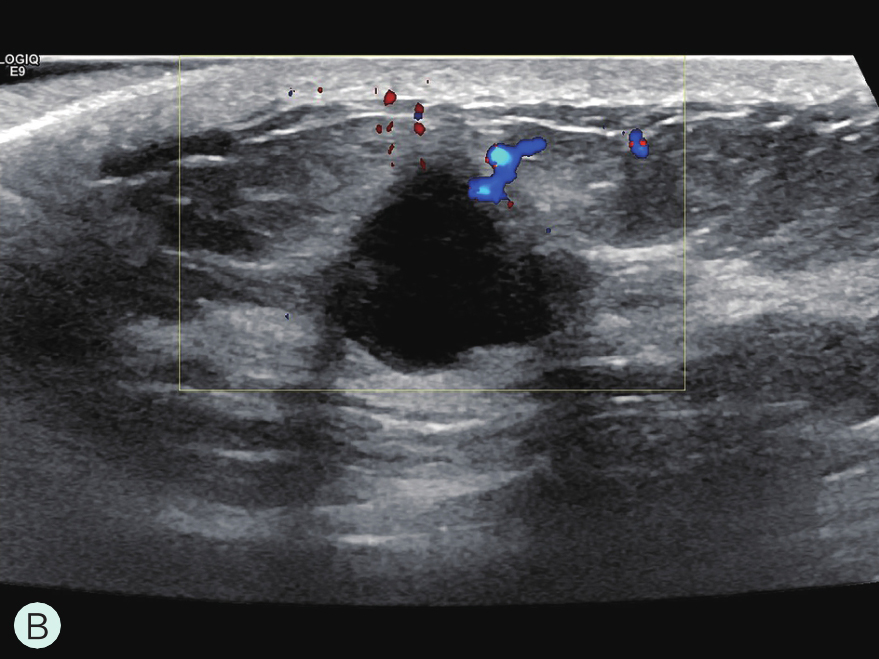

A.病灶二维图像;B、C.病灶CDFI图像;D.同侧腋窝淋巴结情况;E.病灶弹性成像图像

图2-2-1 确定造影病灶

图2-2-5 血流信号最丰富或有滋养血管切面